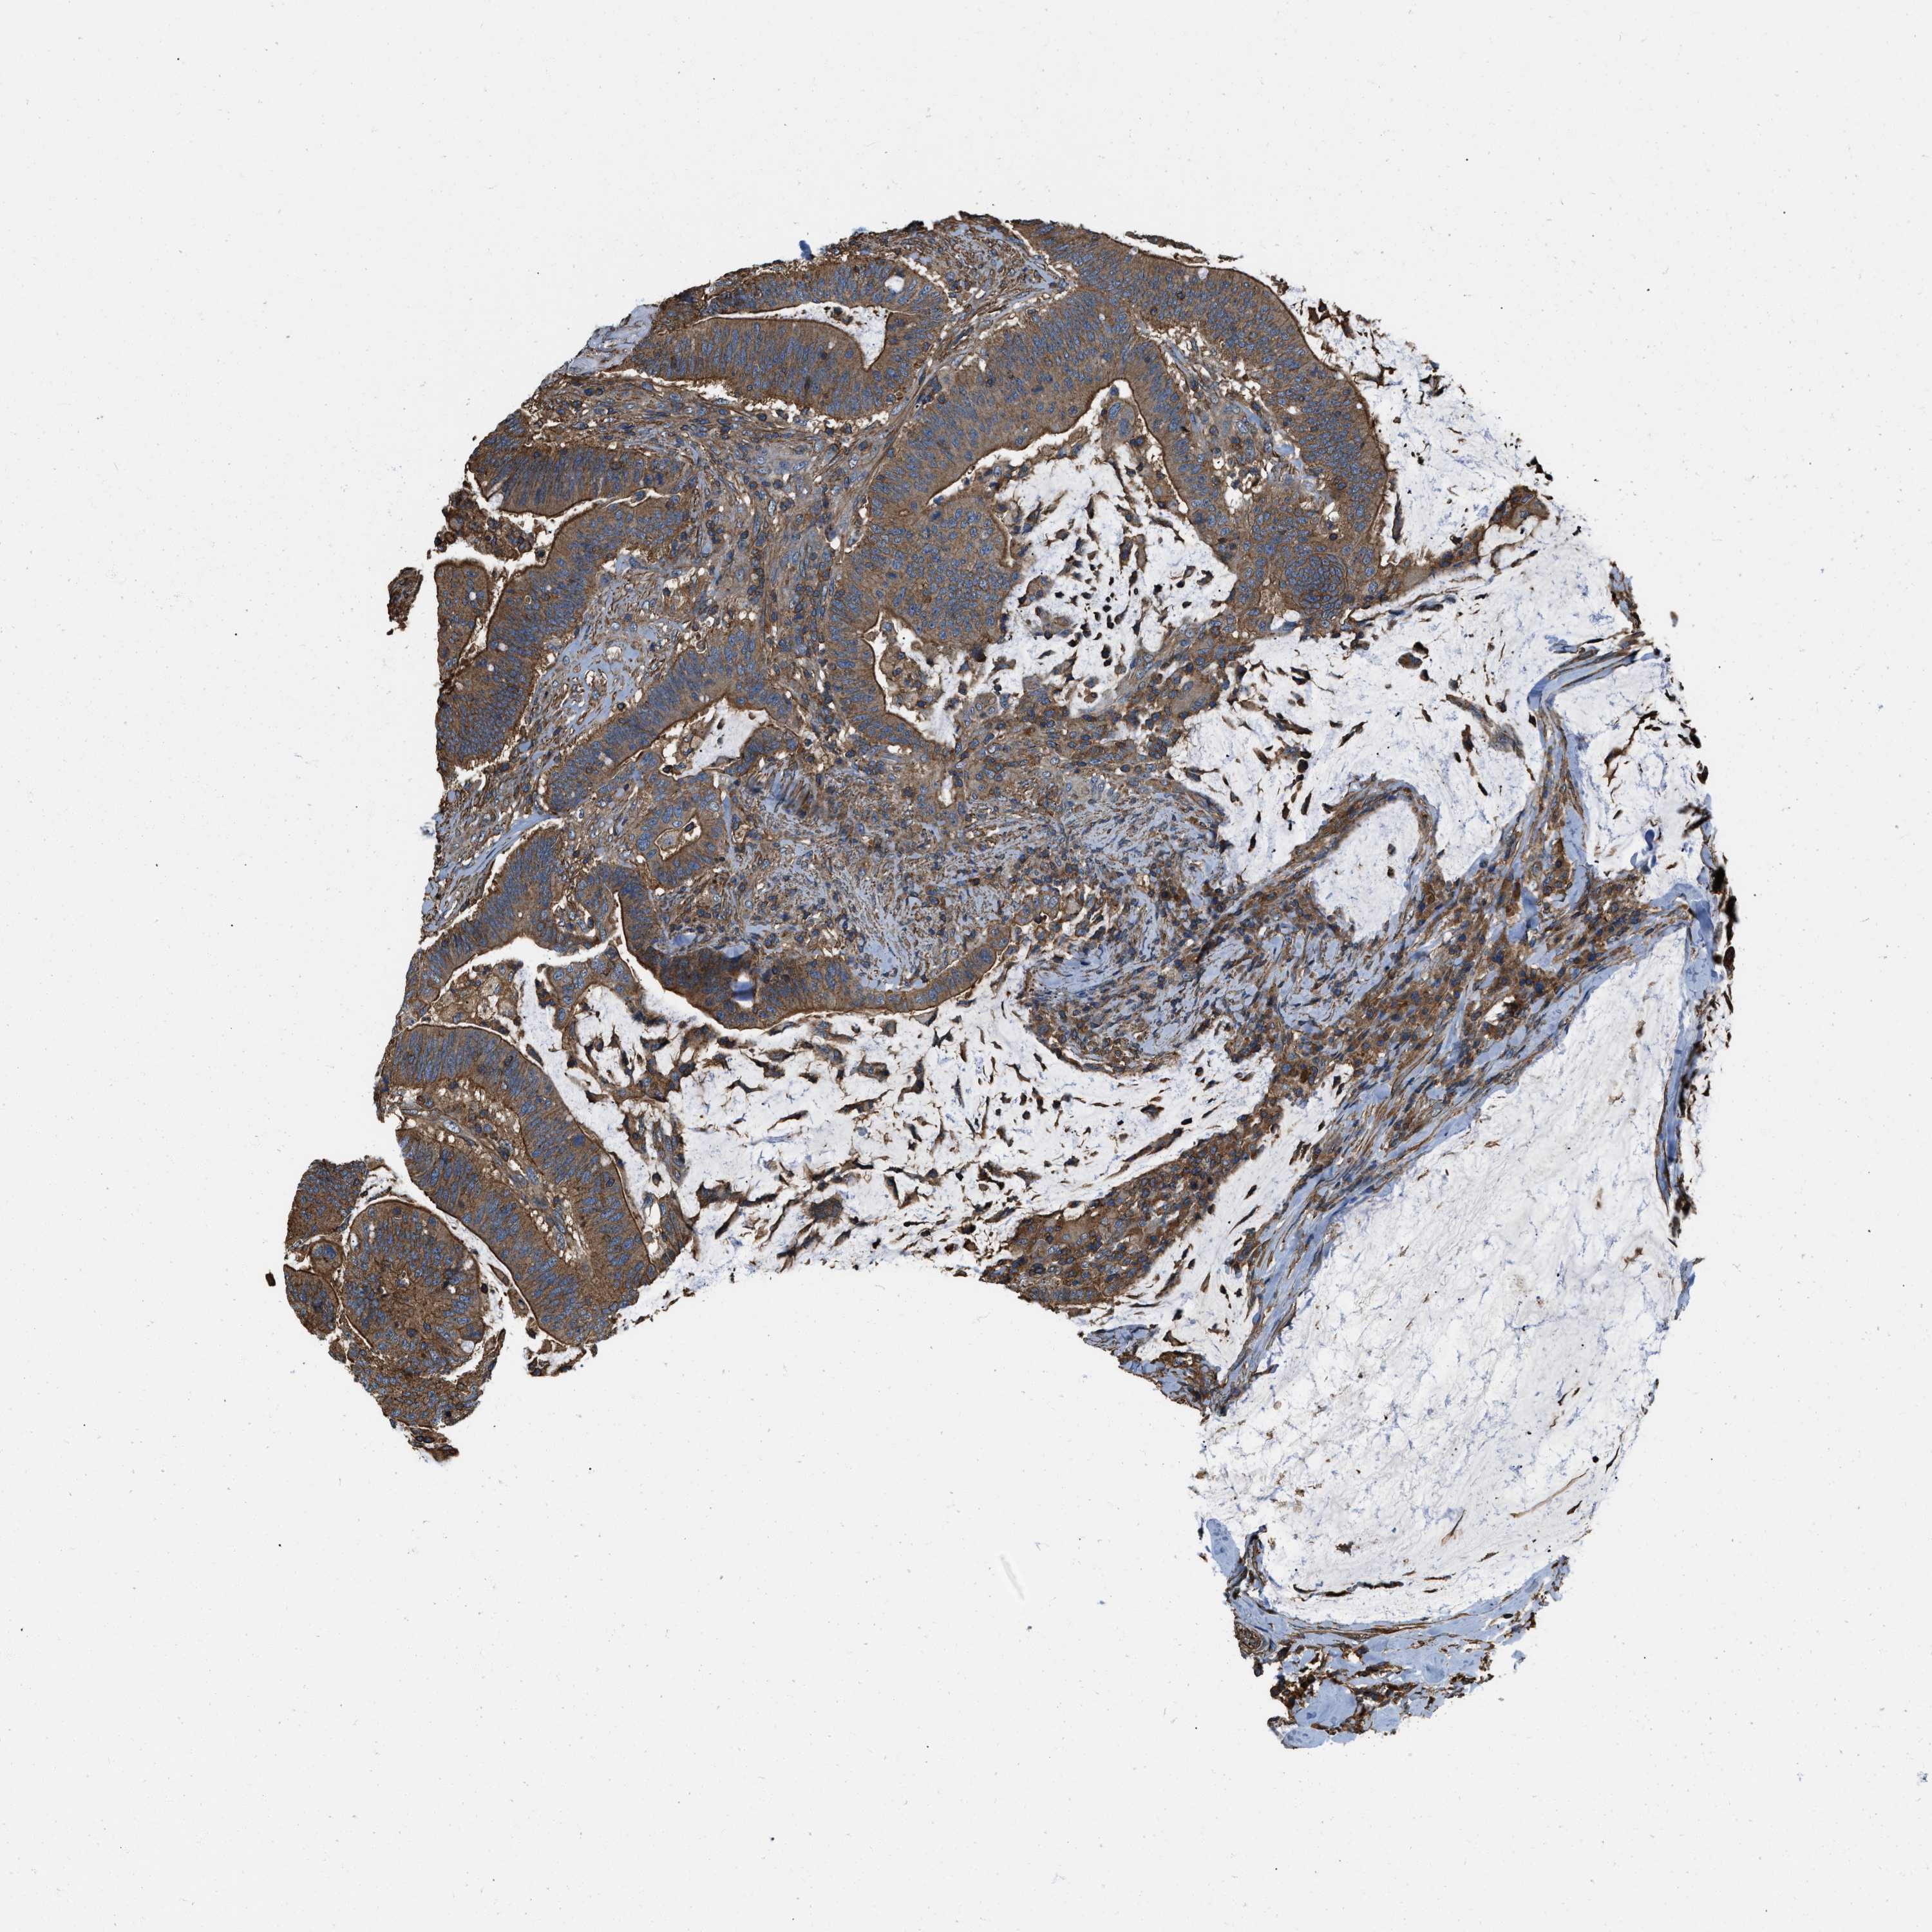

CANCER COLORECTAL CANCER Show tissue menu

Colorectal cancer

Rectum adenocarcinoma